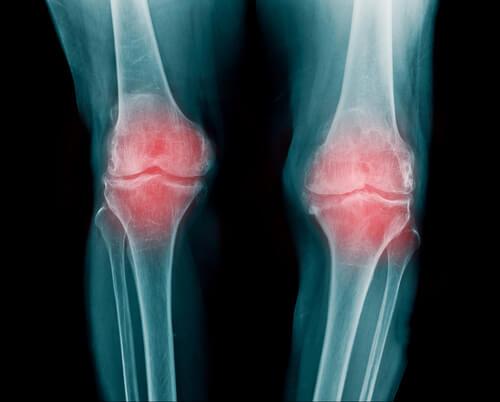

Romatoid Artrit (Eklem iltihabı)

- Romatoid artrit eklemde iltihap oluştuğu anlamına gelir. Pek çok farklı eklem iltihaptan etkilenebilir. Genel olarak parmaklarda, kollarda ve dizlerde oluşur.

- Genelde 30 ile 60 yaş aralığında ortaya çıkar. Kadınlarda daha yaygın olarak görülür. Yaşanan yer veya ırk hastalığın ortaya çıkmasında veya seyrinde herhangi bir farklılık yaratmaz.

- Romatoid artriti olan kişiler kısıtlı bir hareketliliğe sahiptirler. Karıncalanmadan sonra daha kötü ağrılar başlar.